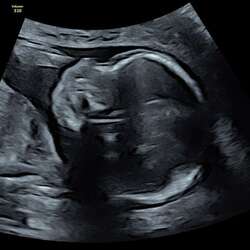

We wouden graag een derde. Stiekem idd zou een meisje leuk zijn. We hebben er voor gekozen om het geslacht niet te weten.

Twee weken geleden is onze derde zoon geboren. Ik voel me zo rijk met drie van die heerlijke mannen. Het voelde ook wel relaxt dat het weer een jongen is. Kleding is al in huis. Speelgoed etc. Niks geen gedoe met staartjes en rokjes. Was het een meisje dan was het ook helemaal super geweest hoor, maar kan me dat nu helemaal niet meer voorstellen.

Zelf ben ik zwanger van mijn 3e, deze keuze was omdat wij nog een kindje wilden en niet per se een meisje, Tuurlijk is het extra bijzonder na 2 jongens.